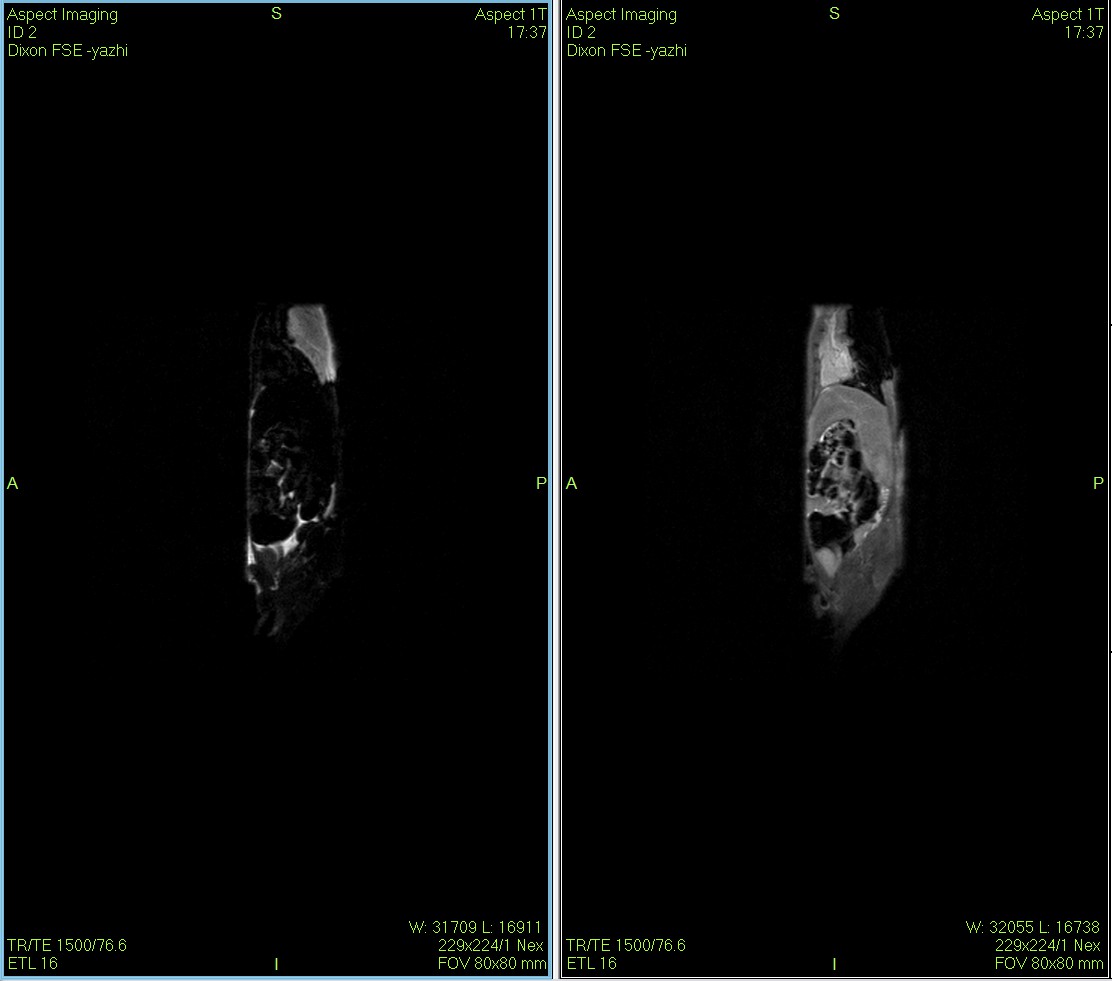

Dixon脂肪抑制技术是由Dixon 提出,其基本原理是利用水、脂肪的化学位移差异,使用不同的回波时问,分别采集水和脂肪质子的in Phase 和 opposed -phase两种回波信号。

低场核磁共振技术,已被广泛应用于小动物(大、小鼠)实验模型中,用于监测体内脂肪分布及沉积情况。这不仅有助于揭示人类肥胖代谢性疾病的病因,还为肥胖治疗药物的评价提供了重要依据。通过低场核磁共振技术结果表征,科研工作者能够直观地观察到小鼠体内脂肪的变化,从而更深入地理解肥胖症的发病机制。